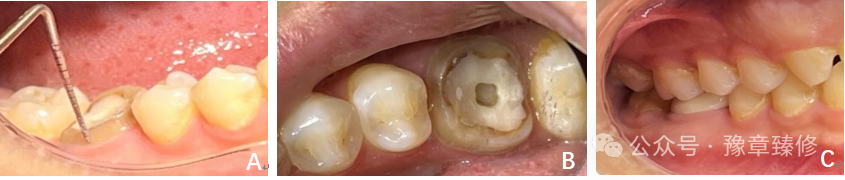

针对髓腔固位深度不足(<3mm)的短冠磨牙,PFRC将修复体向根管内延伸1-2mm,与髓腔固位部分一体成型,使总固位深度达4-5mm,增大粘接面积和机械固位,并优化应力分布(桩分布于颊舌、近远中),有效解决了单纯髓腔固位冠固位不足的问题(图6)[13]。PFRC用于短冠磨牙时,适用于髓腔固位深度不足(<3mm)但需额外根管内固位(延伸1-2mm)的情况。当短冠磨牙根管过度弯曲或根尖未闭合(年轻恒牙)、或根尖周病变未控制(感染风险高),不建议使用PFRC修复。

图6:A-F修复前X线片及临床检查;A:根管治疗术前 X线片;B:根管治疗术后X线片;C:根管治疗术后颊侧近中𬌗龈距离约2mm;D:根管治疗术后颊侧远中𬌗龈距离约2.5mm;E:根管治疗术后舌侧近中𬌗龈距离约2.5mm;F:根管治疗术后舌侧远中𬌗龈距离约3mm。G:𬌗面牙体预备后情况;H:修复体情况;图I-L;2年后复查X线片和口内情况;I:修复后2年复查 X线片;J-L:2年后复查口内情况。